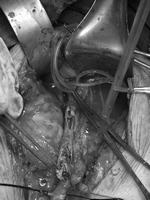

邹大爷转入血管外科后,郑州大学五附院血管外科专家王兵教授高度重视,当即指示主管医师王颖主治医师尽快完善下肢动脉CTA检查(图1),检查结果显示邹大爷双下肢动脉硬化闭塞症,双侧股浅动脉长段闭塞,同时左侧髂外动脉闭塞,缺血严重,导致截肢风险巨大,需尽早手术治疗。虽为双下肢病变,但目前患者左下肢症状突出,考虑到邹大爷年龄较大,合并多发基础疾病,同时手术治疗,手术时间长,麻醉风险大,与邹大爷家属沟通后拟先行处理左下肢病变。但不可规避的问题来了,邹大爷家处农村,经济条件很一般,如果按照理想状态去开通闭塞动脉,首选复合手术,即先行小切口取栓,将长段闭塞变为短段病变,而后行腔内治疗,狭窄或闭塞段行球囊扩张及支架置入,髂动脉及股动脉需分别置入支架,费用高达数万元。这笔费用对于这样一个家庭来说是远远不能承受的。但因为费用问题放弃治疗,邹大爷很快面临的就是截肢,甚至是生命危险!这样两难的境地也是外科医生经常面对的问题。最终,王兵教授凭借自己多年来深厚的外科功底,决定放弃腔内治疗,行传统的内膜剥脱手术,这样既能打通闭塞动脉,又可避免置入支架。同时考虑到邹大爷双侧股动脉闭塞,此次突发左下肢缺血症状,与髂动脉闭塞相关,所以本次手术以解决髂动脉闭塞为主,髂动脉打通后通过股深动脉的代偿,同样可以起到缓解症状的疗效。

图1